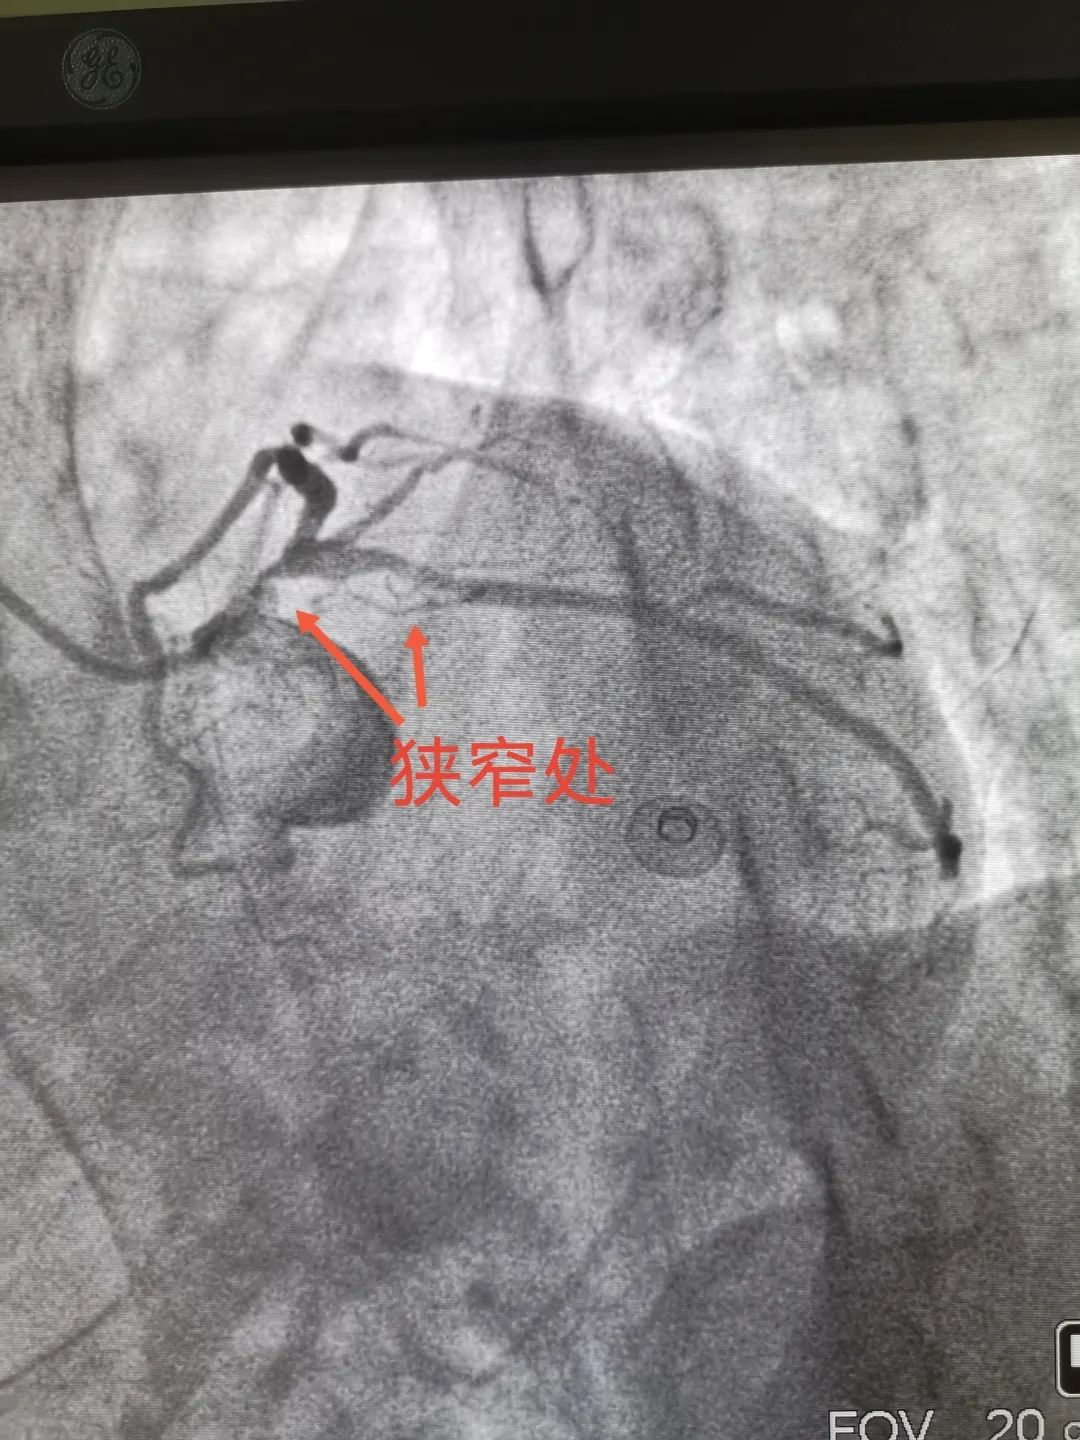

患者左主干重度狹窄,回旋支近段重度狹窄,于是立刻為其植入冠脈支架,目前該患者病情基本穩(wěn)定。